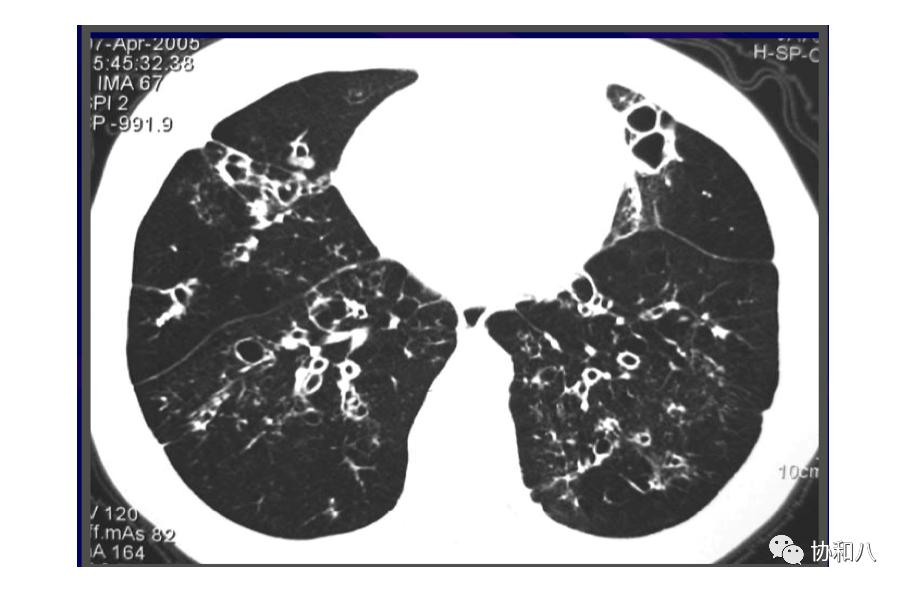

4. 葡萄串征:

常用于描述囊状支气管扩张(图1&2)的典型CT表现,也见于结肠含气囊肿(图3)。描述:簇状/串状囊腔呈葡萄串样。

左滑高能预警